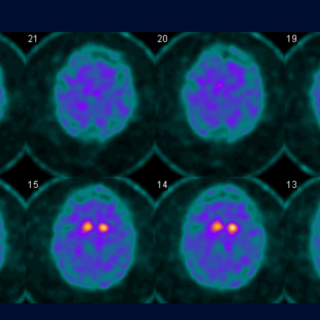

This insight could eventually help doctors diagnose Parkinson’s earlier. Today, identifying the disease often takes years and usually involves a long series of clinical evaluations. A simple smell based test could offer a faster, cheaper and non invasive alternative. Loss of the sense of smell is already known to be…